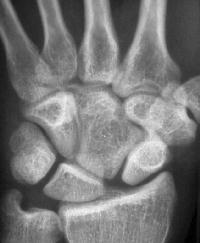

Clinical Example: Congenital capitate malformation with capitate trapezoid articulation and scapholunate diastasis

This patient was evaluated for wrist pain following a wrist sprain.

Plain films demonstrate an unusual capitate contour, articulating with the proximal trapezoid. There is a wide scapholunate interval.